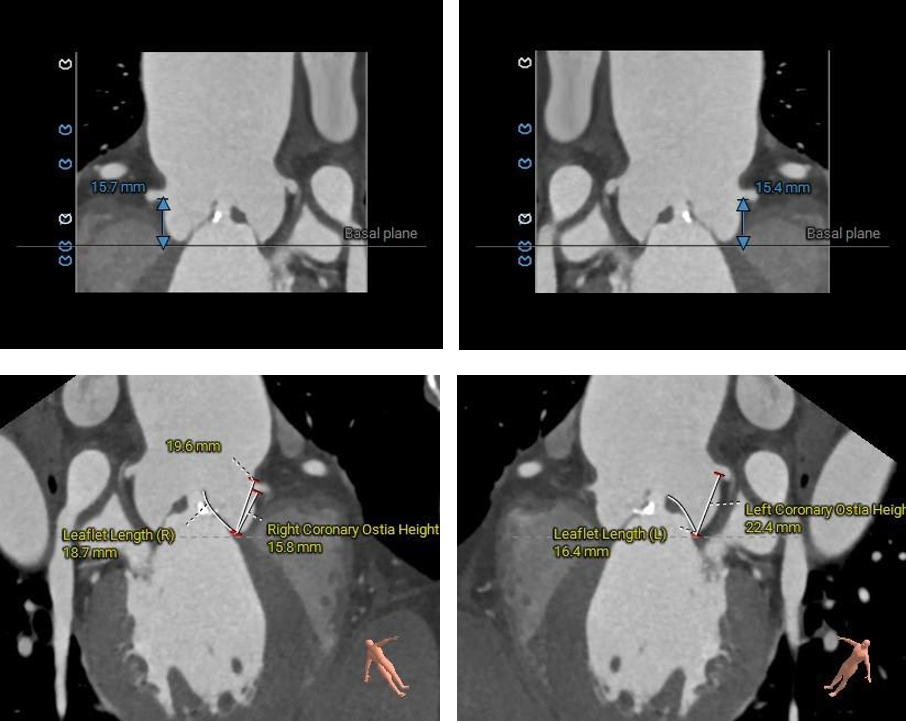

1.主动脉瓣瓣环周长83.8mm,平均周长径26.7mm。

2. Type0型二叶式主动脉瓣,左右冠不同窦,瓣叶中度钙化伴增厚,钙化分布不均匀,主要分布于瓣叶对合缘处。

3. 左右冠开口高度可,左冠瓣叶长度<瓣叶附着缘到冠脉开口处,右冠瓣叶长度>瓣叶附着缘到冠脉开口处,瓦氏窦、窦管交界内径尚可,升主动脉瘤样性扩张(最大直径52.2mm) 。

2. 左右冠开口高度可,左冠瓣叶长度<瓣叶附着缘到冠脉开口处,右冠瓣叶长度>瓣叶附着缘到冠脉开口处,结合瓦氏窦、STJ内径及形态结构综合分析,预估冠脉堵塞风险偏低。